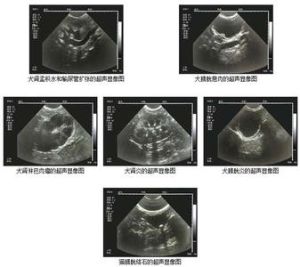

監測卵泡檢查方法:一般情況下,自月經周期的第8天起,每2天B超監測1次,當發現卵泡直徑達17毫米時,應該改每天監測1次,當卵泡發育成熟直徑達20-23毫米時,必要時每天測2次,直至排卵為止。B超探頭頻率3.5MHz每次監測,觀察雙側卵巢大小、形態,記錄卵泡數量、大小,月經第幾天等。

套用B超監測排卵,對於月經周期規則、基礎體溫雙相的不孕婦女,往往以為卵泡發育正常而忽視對其進行進一步檢查,實際上,這類病例中卵泡發育和排卵異常是比較多見的,運用B超監測育齡婦女,特別是不孕婦女卵泡發育詳細情況,確認其有否卵泡發育成熟、有否排卵及排卵時間,為臨床對症治療提供可靠依據是十分重要的。